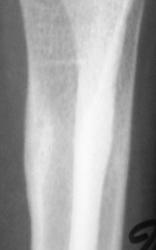

Снимки с более высокой степенью разрешения.

Определяются локальные оссифицированные периостальные наслоения в н/3 диафиза лучевой кости, что-то наподобие дефекта со склеротическим контуром по передней поверхности кости. У меня три варианта: 1 - консолидированный перелом лучевой кости; 2 - патологическая перестройка (читала у Рейнберга, может встречаться в лучевых и локтевых костях, выглядит как консолидированный перелом); 3 - первично-хр. остеомиелит.

Коллеги! меня тоже смущает участок, выделенный Валентином Львовичем стрелочками. Имеются округлой формы, мелкие участки перестройки костной ткани литического типа. Кортикальный слой муфтообразно утолщен с периоссальной реакцией. А нет ли там объемного образования?

Меня тоже смущает, и очень. Отправляйте к детским онкологам, пусть они контролируют. Основание: диафиз лучевой кости бульбообразно расширен ("поддут"), структура кости уплотнена муфтообразно/"пояском", менее выраженные, чем по переднему стенке кости, но аналогичные изменения отмечаются и по задней стенке диафиза, плюс периостальная реакция в прямой проекции.